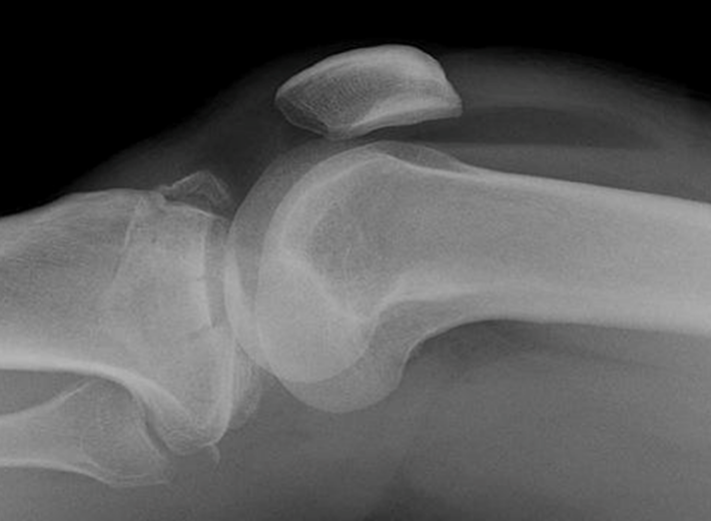

12

Q

What is the diagnosis?

What are some lesions associated with this injury?

A

Anterior shoulder dislocation

Associated with:

• Hill-Sach fracture (60%)

• Flap fracture (15%)

• Bankart lesion

• Labral tear

axillary nerve injury possible